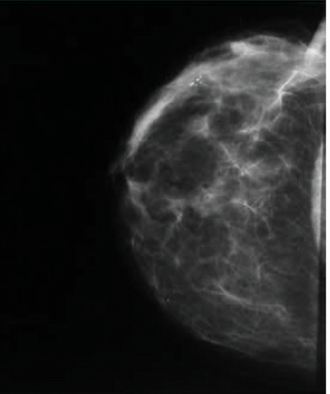

Kazuistika č.5

V HZQ nový shluk mikrokalcifikací, spíše odlitkového charakteru,

různé velikosti, hodnoceny jako maligní – dle

histologie po exstirpaci po označení vodičem invazivní duktální karcinom